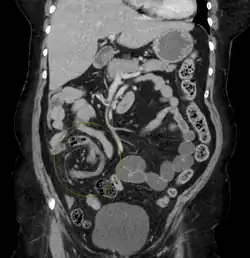

Coronal CT of the abdomen, demonstrating a volvulus as indicated by twisting of the bowel stock | |